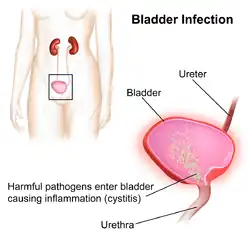

A urinary tract infection (UTI) is an infection that affects a part of the urinary tract.[1] Lower urinary tract infections may involve the bladder (cystitis) or urethra (urethritis) while upper urinary tract infections affect the kidney (pyelonephritis).[10] Symptoms from a lower urinary tract infection include suprapubic pain, painful urination (dysuria), frequency and urgency of urination despite having an empty bladder.[1] Symptoms of a kidney infection, on the other hand, are more systemic and include fever or flank pain usually in addition to the symptoms of a lower UTI.[10] Rarely, the urine may appear bloody.[7] Symptoms may be vague or non-specific at the extremities of age (i.e. in patients who are very young or old).[1][11]

Lower urinary tract infection is also referred to as a bladder infection. The most common symptoms are burning with urination and having to urinate frequently (or an urge to urinate) in the absence of vaginal discharge and significant pain.[4] These symptoms may vary from mild to severe[10] and in healthy women last an average of six days.[19] Some pain above the pubic bone or in the lower back may be present. People experiencing an upper urinary tract infection, or pyelonephritis, may experience flank pain, fever, or nausea and vomiting in addition to the classic symptoms of a lower urinary tract infection.[10] Rarely, the urine may appear bloody[7] or contain visible pus in the urine.[21]

The bacteria that cause urinary tract infections typically enter the bladder via the urethra. However, infection may also occur via the blood or lymph.[7] It is believed that the bacteria are usually transmitted to the urethra from the bowel, with females at greater risk due to their anatomy.[7] After gaining entry to the bladder, E. Coli are able to attach to the bladder wall and form a biofilm that resists the body's immune response.[7]